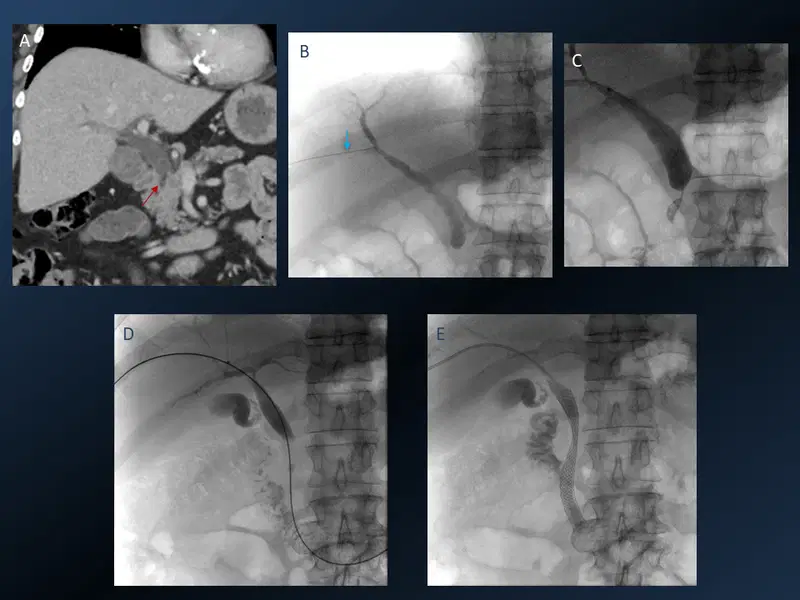

Percutaneous Transhepatic Biliary Stenting Interventional Radiology

CT scan (A) showing distal CBD cholangiocarcinoma (red arrow) resulting in biliary obstruction. US guided biliary access using a Chiba needle (B, blue arrow) and Cholangiogram confirmed distal CBD obstruction (C). This was eventually crossed using a hydrophilic guidewire (D) and a self expanding metallic CBD stent was placed into the duodenum (E).